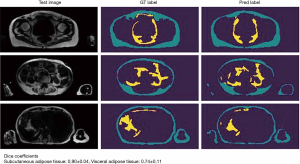

Parallel to advantages in the application of CT for BCP tasks, MRI has gained comparable importance in the assessment of body compartments, muscle mass, and associated anthropometric measures. The technique is free of ionizing radiation and therefore allows repetitive scans in specific longitudinal observations. Furthermore, free from several technical biases or errors in DEXA and CT, MRI has been validated to reliably measure body compartments (16,17), and to perform this task at high accuracy, given a range of quantitative error of 1.1% to 4.4% (18). This error may also depend on basic acquisition parameters, such as the use of surface or body coils or other protocol decisions (e.g., continuous moving table acquisition; see Table 1 for exemplary protocol) with implications on signal-to-noise ratio and acquisition time. This must be considered and handled individually, as an error of a few percent may be negligible for certain populations and indications while playing a significant role in e.g., monitoring examinations of athletes. In any case, despite its validity and reliability, MRI currently faces difficulties in availability and ease of use in terms of data assessment. The big advantage of muscle assessment by MRI, namely acquisition of whole-body data, demands technically difficult and still time-consuming post-processing. Manual segmentation, as shown in Figure 1 takes several hours (depending on the volume, accuracy, and detail of segmentation) but is currently not ready-for-use in clinical practice. Numerous automated methods intend to ease whole-body segmentation (20-22), but except for very limited proprietary examples, the majority of BCP assessment by whole-body MRI is currently performed in research settings employing artificial intelligence for advanced segmentation tasks with promising results (Figure 2).

Another challenge is the huge amount of MRI data per whole-body scan. A typical whole-body MRI produces 400 to 500 images per composed series (e.g., in-phase, opposed-phase, fat-only- or water-only-images). Without robust and fast automated segmentation solutions, BCP assessment with whole-body MRI will be very time consumption up to several hours per patient, which is far more than an average clinical radiologist is allowed to spend for one examination. Alternatives to whole-body solutions may, however, focus on the investigation of data reproducibility that is derived from representative single- or few-slice segmentations. The most representative single slice region of whole-body compartments is believed to be on a lumbar spine level. More specifically, Schweitzer et al. suggest the level of the third lumbar vertebra as optimum in terms of reproducibility and correlation with body compartments (102). As mentioned before, likewise approaches may be a legitimate strategy for a restricted spectrum of clinical tasks, e.g., initial sarcopenia assessment in an opportunistic screening setting. However, the aspect of reduced accuracy must be considered carefully for the majority of clinical demands. Most importantly, more recent studies have proven the inferiority of single-slice technique compared to whole-body compartment assessment, and this method furthermore lacks the required reproducibility for e.g., longitudinal studies, as demonstrated by recent CT-, and more recently MR-related investigations (103,104). Another strategy in assessing these large data amounts is the utilization of automatic registration and segmentation algorithms. Especially within the last few years and rising with the use of artificial intelligence in radiology, several groups have made efforts in testing different segmentation concepts for whole-body imaging, muscle and fat compartment assessment. While the first studies mostly focused on CT images, an increasing body of literature has recently focused on automated segmentation of different regions and for different radiologic subspecialties in MR and CT as well. A recently published review article describes 408 included original papers that aimed to automatically segment tissue (20). For the musculoskeletal system, Dice similarity coefficients around 0.9 are currently being achieved (20). While most of these applications are limited to research questions, it may be expected, that also due to improvements of expertise among the radiologic community regarding implementation of machine learning these algorithms will be part of clinical routine soon.